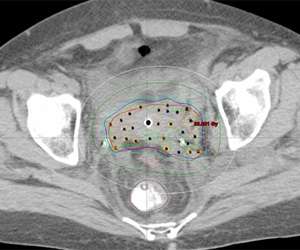

An alternative to this is to use CT compatible applicators and to use CT imaging. The advantage of this is that CT imaging allows you to see the anatomy in more detail than on X-rays. For example, a CT image with a vaginal applicator in place looks like the following:

CT Scan

One can actually "see" the anatomy including the bladder (yellow) and rectum (brown). The cylinder is outlined in red. By being able to clearly see things we can more effectively optimize the radiation dose to the target and limit the dose to normal tissues.